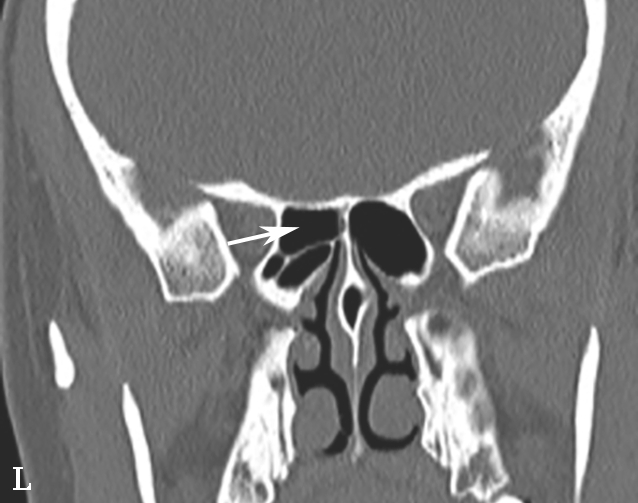

蝶窦常见解剖变异包括:①有分隔的蝶窦,可为纤维或骨性分隔分成几个不对称的部分,此变异容易导致蝶窦手术引流不完全而残留病变;②介甲型蝶窦,窦腔略有气化,发育很小,窦腔后缘与鞍结节垂直线之间尚有10mm厚骨质;③鞍前型蝶窦,蝶窦发育较小,窦腔后缘与鞍结节垂直线相齐,恰好位于蝶鞍之前,蝶鞍底大部分为松质骨;④半鞍型蝶窦,发育尚好,后上缘占鞍底前半部;⑤全鞍型蝶窦,发育良好,自鞍结节至鞍背连线的全鞍底与蝶窦只一层薄骨板;⑥枕鞍型蝶窦,与全鞍型相似,但发育更大,后缘超过鞍背垂线,蝶窦侵入枕骨使斜坡骨板更薄(图1-3-7)。

图1-3-7 蝶窦及蝶窦区解剖变异

A.颈内动脉管突入蝶窦;B.蝶窦间隔(白箭);C.左侧翼突气化;D.蝶嵴(星)、蝶骨大翼(白箭)、鞍背气化(虚箭);E.蝶骨小翼气化(白箭);F、G.鞍前型蝶窦(三角);H、I.甲介型蝶窦;J、K.鞍型蝶窦;L.Odoni气房(白箭)